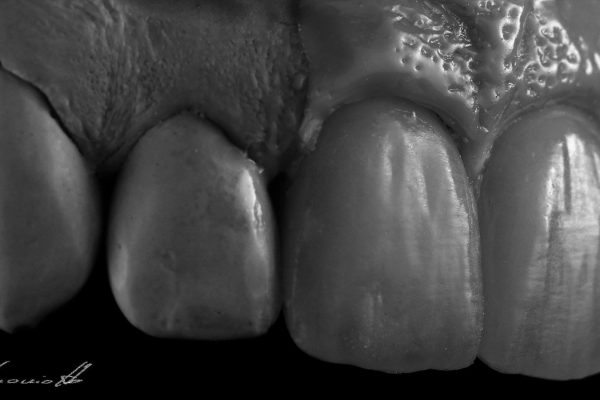

The BioCeramiche, realized by us, are protected in their recipe and manufacturing process by THREE INTERNATIONAL PATTENTS of our exclusive property (n° 01315293 – 01307082 – 01343575 Submitted to the Ufficio Italiano Brevetti) .

We are therefore able to create Unique, Personalized, and Original products